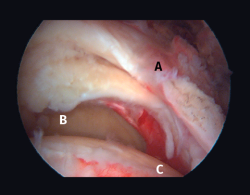

Figura 4. Rotura de supra- e infraespinoso en forma de L invertida con presencia de 2 capas. A: tendón supraespinoso; B: tendón infraespinoso; C: cabeza humeral.

Figura 10. Grado 2 de la clasificación de Patte. A: rotura retraída del tendón supraespinoso; B: glena; C: cabeza humeral.